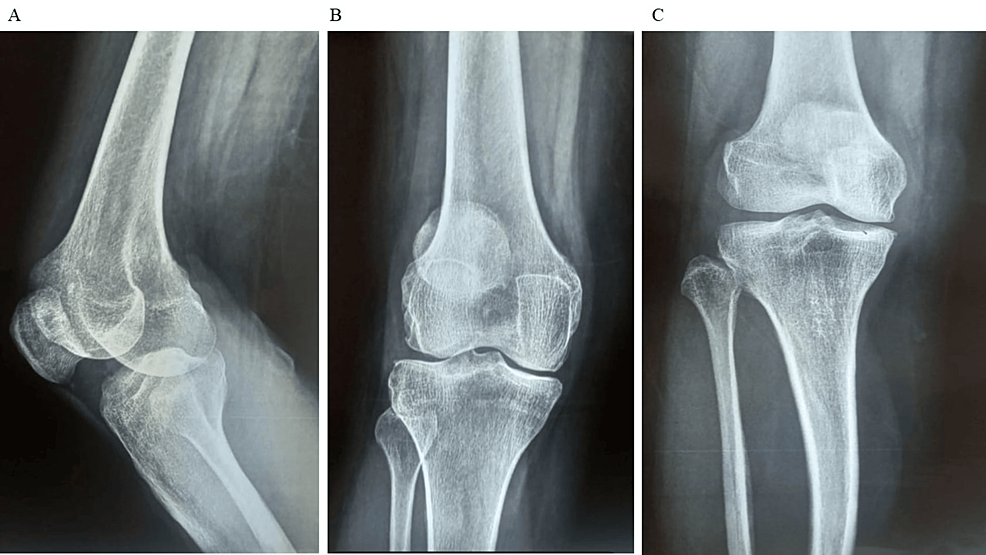

除了骨關節炎外,15名參與者還被發現患有骨缺損,占該隊列的30%。這些缺損包括各種情況,例如骨折、退行性骨病或先天性畸形,突顯了研究中涉及的骨科問題多種多樣。下圖1顯示了開始干細胞治療之前的骨骼側視圖和前后視圖。